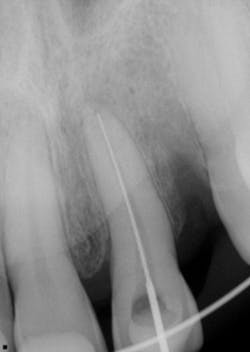

Twelve days later, the patient returned with the following assessment and treatment (figure 4):

- Overall, the patient was feeling better, with reduced swelling in all soft-tissue areas.

- Chief concern: His bite was off. This was adjusted.

- Cold testing: No response with No. 9 and slight delay with No. 8.

- Tooth appeared more stable within the alveolus; the splint was removed between Nos. 8 and 9, but not from canine to canine.

- It was recommended that we commence with endodontic treatment on No. 9 and maintain a watch on No. 8 for any irreversible changes.

- Tooth No. 9 was opened up; the pulp was necrotic. The chamber was cleaned out, irrigated, and calcium hydroxide medicament was placed. It was recommended that we change out the dressing two to three more times over the course of the next few months, so stabilization of the tooth could continue and a better prognosis could be determined.

Figure 4